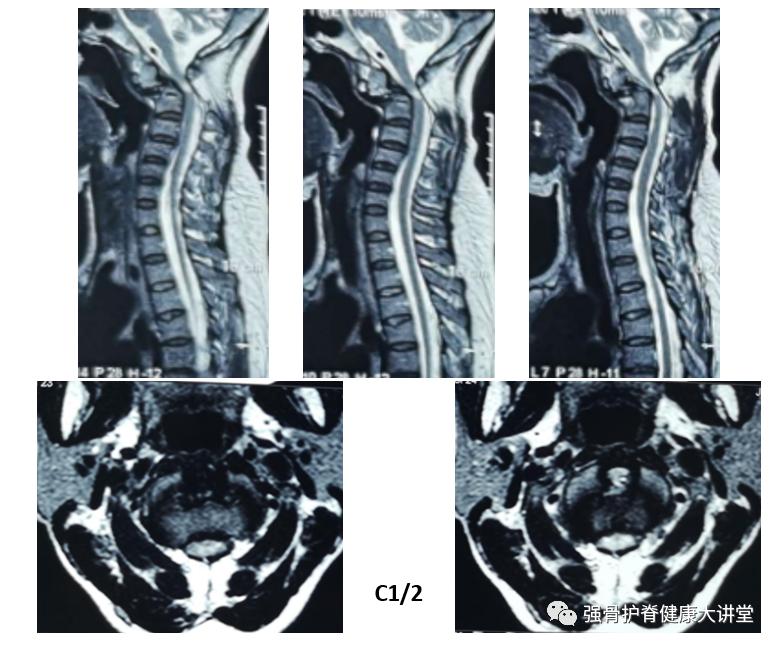

【术前资料】

颈椎中立位MRI

颈椎过伸位MRI

结合患者病史、症状体征及影像学检查,明确诊断为:1.寰枢椎脱位 2.颈部脊髓损伤 3.陈旧性颈椎骨折(齿状突) 经认真术前评估后,在梁德教授指导下,江晓兵教授带领团队为其施行前路显微镜下经口寰枢椎松解、枢椎齿状突骨赘磨除、后路C1滑脱复位、C1-C2后方植骨融合内固定术。

该患者为寰枢椎脱位,伴有陈旧性齿状突骨折及颈脊髓损伤。术前过伸位CT和MRI显示寰枢椎稍复位,而复位后椎管狭窄无明显改善,又枢椎骨折端存在较多骨赘,如单纯后路完全复位后恐骨赘突入椎管,加重脊髓损伤。因此,该案例需要前后路联合手术,先行前路经口撬拨枢椎骨折端进行松解同时清除骨赘,一是便于后路寰枢椎脱位复位,二是防止骨赘在复位过程中损伤后方脊髓。寰枢关节后方毗邻生命中枢延髓,进行手术治疗是恢复上颈椎正常序列、解除神经压迫、挽救患者生命的关键选择。